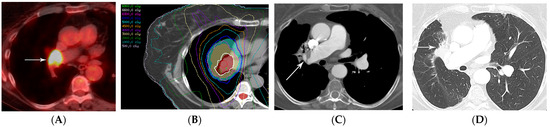

2.2. Three-Dimensional Conformal Radiotherapy

2.3. Intensity-Modulated Radiotherapy

2.4. Stereotactic Body Radiotherapy

2.5. Four-Dimensional Conformal Radiotherapy